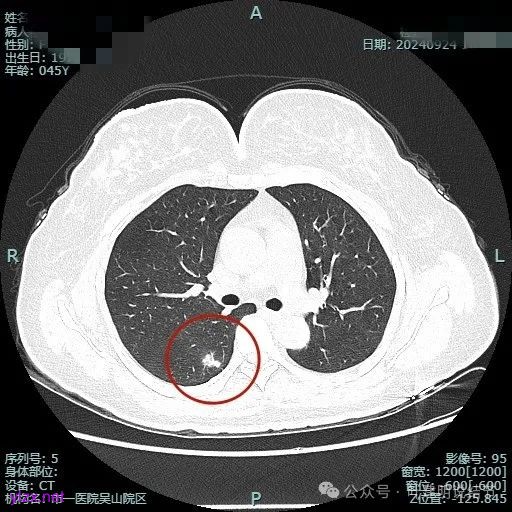

我们先来看2024年9月时的影像:

病灶1:

右下背段混合密度病灶,边上不太清爽,有片状淡磨玻璃影,实性部分密度较高。

感觉病灶有点晕征似的,表面不平,灶内不太致密。

有小血管进入,似有晕征。

离胸膜近但牵拉不明显,病灶边缘有细毛刺,较短且不太锐利。

边缘少许磨玻璃成分,血管进入明显。

瘤肺边界稍显不清。